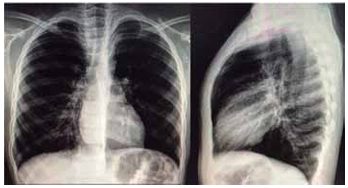

Após todas essas medidas, paciente segue com desconforto respiratório, FR = 44 ipm, SatO2 = 94% em máscara; ausculta pulmonar com o mesmo padrão inicial. Realizada radiografia de tórax a seguir.

(Arquivo pessoal; imagem usada com autorização)